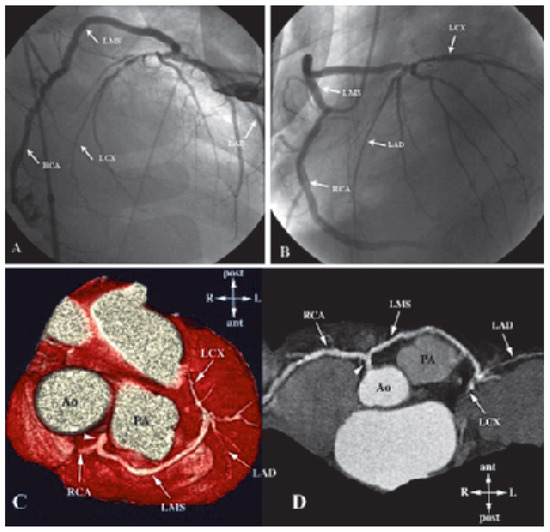

The incidence of heart failure is increasing and patients are threatened to die of pump failure as well as of sudden cardiac death (SCD). Lately, cardiac resynchronisation therapy (CRT) has been introduced to treat patients with persistent heart fail...